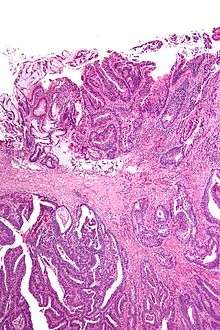

Micrograph showing a positive cauterized surgical margin in an adenocarcinoma (center-top of image). H&E stain.

Surgical margin, also known as tumor free margin, free margin, normal skin margin, and normal tissue margin, usually refers to the visible normal tissue or skin margin that is removed with the surgical excision of a tumor, growth, or malignancy.

Surgical margin in a surgery report defines the visible margin or free edge of "normal" tissue seen by the surgeon with the naked eye. Surgical margin as read in a pathology report defines the histological measurement of normal or unaffected tissue surrounding the visible tumor under a microscope on a glass mounted histology section.[1][2] A "narrow" surgical margin implies that the tumor exists very close to the surgical margin, and a "wide" surgical margin implies the tumor exists far from the cut edge or the surgical margin. Narrow surgical margin using the bread loafing technique suggests that residual cancer might be left due to false negative error. A surgeon often will perform a second surgery if a narrow surgical margin is noted on a pathology report.